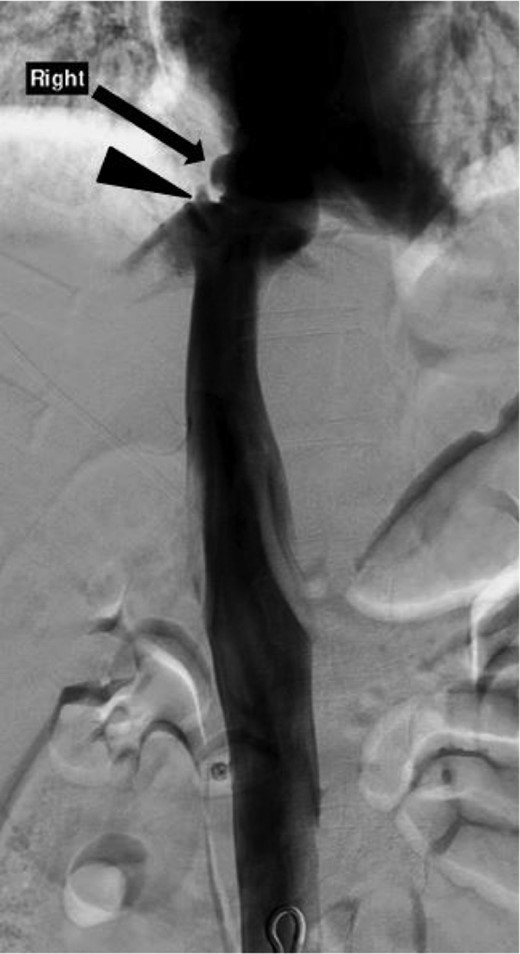

Inferior venacavagram showing a mild contour irregularity of the suprahepatic IVC without contrast extravasation (arrow) and a slight contour irregularity of the middle hepatic vein without contrast extravasation (arrowhead) consistent with a pseudoaneurysm of the IVC and right middle hepatic vein.